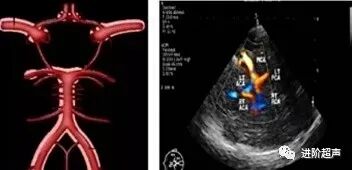

Willis环

又被称为大脑动脉环。它是颅内最重要的侧支循环途径,将双侧大脑半球和前、后循环联系起来。由双侧大脑前动脉始段、双侧颈内动脉末端。两侧大脑后动脉及前、后交通动脉连通而成。

Willis环结构

双侧颈内动脉(ICA)末端

双侧大脑前动脉(ACA)A1段

双侧大脑后动脉(PCA)P1段

前交通动脉(ACoA)

后交通动脉(PCoA)

Willis环解剖结构与TCCD图像对照